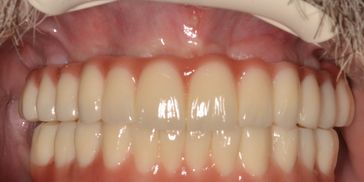

The All-on-4 and All-on-6 concepts are immediate-function protocols for the rehabilitation of the completely edentulous (toothless) jaw. These procedures allow for the placement of a full-arch fixed prosthesis on four or six dental implants, often avoiding the need for extensive bone grafting.

The All-on-4® and All-on-6 concepts are advanced surgical and prosthodontic protocols designed for the immediate rehabilitation of patients with completely edentulous jaws or those with failing dentition.

Immediate Function and "Teeth in a Day"Unlike traditional implant protocols that may require months of healing without teeth or with a removable denture, these concepts allow for

Immediate Loading. A temporary fixed full-arch prosthesis is typically delivered within 24 to 72 hours of surgery. This dramatically shortens the treatment timeline and ensures patients regain aesthetics, speech, and chewing function almost immediately.

A Proven Protocol with Decades of SuccessPioneered in the 1990s and clinically documented for nearly three decades, this technique has revolutionized full-arch rehabilitation. Long-term studies report cumulative success rates exceeding 95-98%, validating it as a predictable, gold-standard solution.